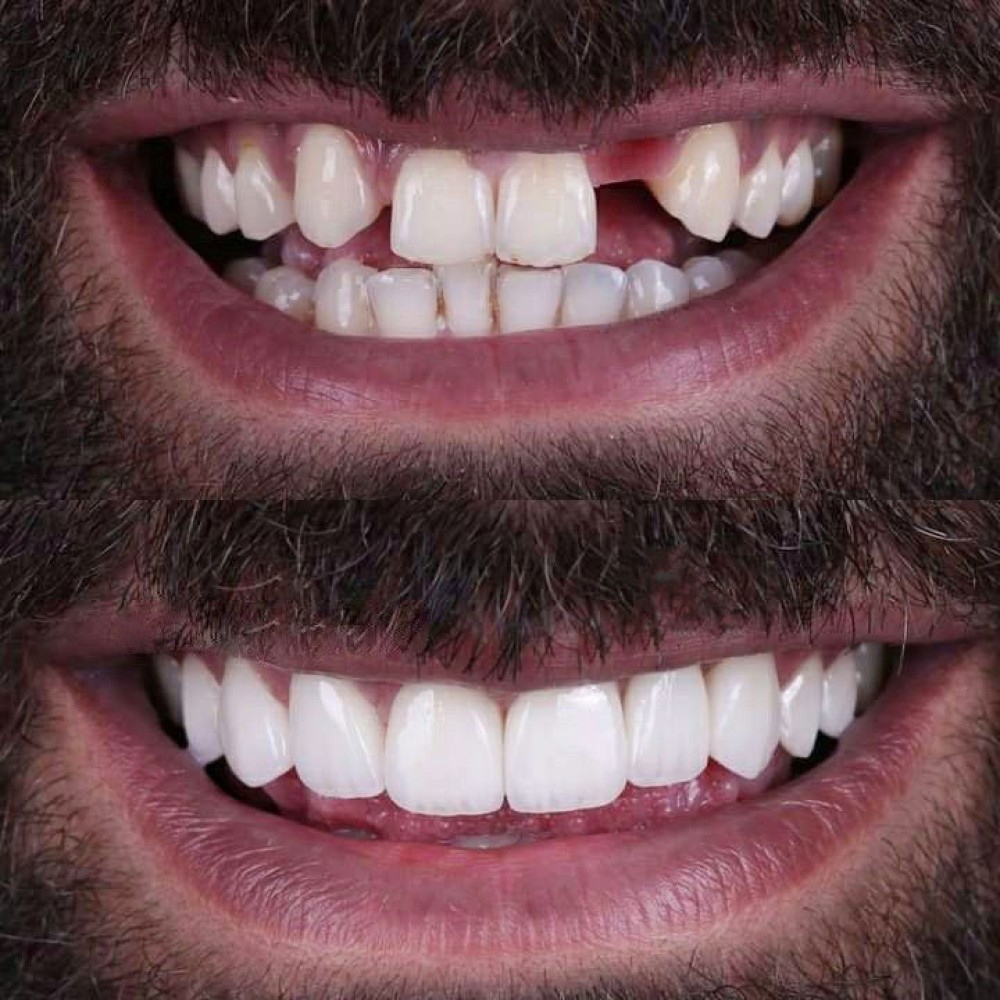

آیا شما هم از مشکلات دندانهای از دست رفته رنج میبرید؟ آیا دندانهای شما از نظر زیبایی یا عملکرد دچار مشکل شدهاند؟ اگر جواب شما بله است، وقت آن رسیده که راهحل بلندمدت و مؤثری را پیدا کنید.

ایمپلنت دندان، نهتنها ظاهری طبیعی و جذاب به شما میدهد بلکه به طور چشمگیری کیفیت زندگی شما را بهبود میبخشد. این روش پیشرفته میتواند جایگزینی دائمی برای دندانهای از دست رفته باشد، که به شما اجازه میدهد دوباره با اعتماد به نفس بخندید، بخورید و حرف بزنید.

با ایمپلنت دندان، نه تنها ظاهر خود را بهبود میبخشید بلکه سلامت دهان و دندان شما هم به شکل قابل توجهی بهتر میشود. ایمپلنتها از تحلیل استخوان جلوگیری میکنند و باعث حفظ ساختار طبیعی فک و دهان میشوند.